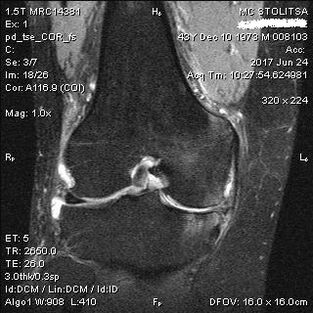

The diagnosis of arthrosis of the knee joint is made in the office of a rheumatologist or orthopedist.The doctor examines the affected joint, palpates it, listens to complaints and asks additional questions.Performs several tests - for example, asks the patient to bend a leg or walk a few steps.Then, if it is necessary to clarify the stage of the disease or the nature of pathological changes, they will refer you to additional studies.For example, for computed tomography or radiography.